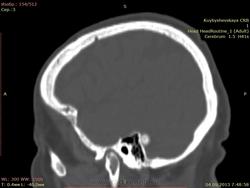

дополнительное образование высокой плотности справа. подскажите

пациентка жалуется на головные боли, больше справа. Подскажите что это за образование справа? первый раз вижу. и деструкции стенки вроде бы нет. плотность высокая.

Остема или небольшая обызвествленная менингиома, что почти одно и тоже. Да менингиому на первое место надо было поставить :)

По-моему обызвествлённая менингиома.

+1. Менингиома.

Стандартное место для менингиомы

Ага, задней грани пирамиды, как некоторые пишут.

ОЧЕНЬ ИНТЕРЕСТНО, А ЧТО В ИТОГЕ. КАК ЗАКЛЮЧЕНИЕ ПИСАТЬ : ОСТЕОМА? МЕНИНГЕОМА?

ЧТО РЕКОМЕНДОВАТЬ, ДИНАМИКА ЧЕРЕЗ СКОЛЬКО ВРЕМЕНИ?